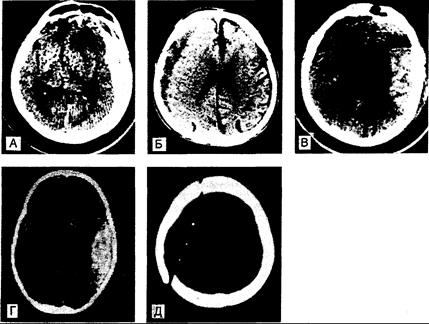

Рис. 344-1. Компьютерные томограммы больных с черепно-мозговой травмой. а — острые субдуральные гематомы со сдавлением прилежащей ткани мозга; б — хроническая субдуральная гематома, рентгенологически менее плотная, чем ткань мозга; в — контузионно-травматическое кровоизлияние в лобной и теменной долях; г — эпидуральная гематома, вызванная переломом с разрывом средней оболочечной артерии. Типичное чечсвицеобразное очертание кровоизлияния; д — переломы черепа по ходу траектории движения пули. Изменение окон при анализе КТ даст преимущество в визуализации переломов и рентгенологически плотных объектов. При этом изображение напоминает простую рентгенограмму.

При компьютерной томографии места ушибов проявляются в виде расплывчатых участков повышенной яркости, соответствующих зонам кортикальных и субкортикальных кровоизлияний с сопутствующим отеком мозга, обусловливающим смещение прилежащих структур, в частности боковых желудочков мозга (рис. 344-1, в). Несколько часов спустя окружающая отечная ткань визуализируется в виде кольца низкой плотности. Сливающиеся, приближающиеся к округлой форме места ушибов можно отдифференцировать от зон спонтанных внутримозговых кровоизлияний по той особенности, что первые распространяются до поверхности коры. В отдельных случаях через неделю вокруг области ушиба при контрастном усилении можно выявить кольцевидное образование, которое ошибочно принимают за опухоль или абсцесс. Глиальные и макрофагальные реакции, начинающиеся в течение 2 дней, спустя год вызывают образование рубцовых наполненных гемосидерином углублений на поверхности мозга (plaques jaune), служащих одной из причин посттравматической эпилепсии. Крупные одиночные кровоизлияния после небольшой травмы возникают у больных с геморрагическими диатезами или лиц пожилого возраста. Иногда они бывают обусловлены амилоидозом сосудов головного мозга.

Острая субдуральная гематома. Симптомы острой субдуральной гематомы возникают спустя минуты или часы после травмы. В состоянии примерно 1/3 больных отмечается светлый промежуток до последующего наступления комы, но у большинства из них сомнолентность или кома развиваются уже с момента травмы. Больные, приходящие в себя, жалуются на головную боль на стороне поражения, зрачок на этой же стороне у большинства из них часто бывает несколько расширен, но в 5—10% случаев расширение зрачка наблюдается контрлатерально по отношению к гематоме. Ступор или кома с односторонним расширением зрачка служат важными симптомами при крупных гематомах. Латерализованные симптомы, такие как гемипарез, могут выявляться на той же стороне, где локализуется гематома, однако оказать помощь при постановке диагноза они могут лишь у некоторых больных. Внезапные эпилептические припадки или изолированные гемианопсии встречаются редко. При КТ обнаруживают сгусток крови, что дает возможность своевременно его удалить (см. рис. 344-1, а). При ангиографии в косых проекциях также можно выявить субдуральную гематому, и этот метод применяют, если нельзя осуществить КТ. Если состояние пациента резко ухудшается, у него происходят быстрое угнетение сознания и расширение зрачка, то до радиологического подтверждения субдуральной гематомы следует наложить трепанационные отверстия или осуществить неотложную краниотомию. Для больных алкоголизмом и лиц пожилого возраста характерен подострый синдром, при котором сонливость, головная боль, дезориентация и легкий гемипарез развиваются в период от нескольких дней до 2 нед после травмы.

Локализация эпидуральных гематом объясняется их происхождением из разорвавшихся сосудов твердой мозговой оболочки, чаще всего средней оболочечной артерии. Поэтому сгустки крови в эпидуральном пространстве располагаются над боковой поверхностью височной доли. У большинства больных имеются переломы сквамозной части височной кости по ходу разорвавшегося сосуда. Реже наблюдаются эпидуральные гематомы, локализующиеся в лобной, нижневисочной и теменно-затылочной областях и развивающиеся в тех случаях, когда переломы приводят к разрывам ветвей средней оболочечной артерии. Иногда разрывы твердой мозговой оболочки, проходящие через сагиттальный или боковой синусы, а также разрывы мелких диплоэтических вен вызывают эпидуральные венозные кровоизлияния. Эпидуральные гематомы отслаивают плотно прикрепленную твердую оболочку мозга от внутренней поверхности костей черепа, формируя сгусток, который на компьютерных томограммах имеет характерные чечевицеобразные очертания (см. рис. 344-1, г). Они относительно редко встречаются среди лиц пожилого возраста в связи с более тесным прикреплением твердой мозговой оболочки к черепу, что характерно для лиц преклонного возраста. Эпидуральные гематомы задней черепной ямки также встречаются редко и клиническая диагностика их затруднена; как правило, они появляются в результате хирургических операций, например, по удалению невриномы слухового нерва.

При рентгенографии черепа не находят каких-либо изменений, за исключением смещения в сторону кальцифицированного шишковидного тела; иногда неожиданно может быть выявлен перелом. При КТ без введения контрастного вещества обычно видно объемное образование низкой плотности над конвекситальной поверхностью полушария (см. рис. 344-1, б), но иногда обнаруживают лишь смещение срединных структур и сдавление боковых желудочков, поскольку рентгеновская плотность сгустка крови постепенно выравнивается с таковой прилежащей ткани мозга — это происходит спустя 2—6 нед. Хронические двусторонние гематомы часто могут остаться незамеченными из-за отсутствия бокового смещения ткани. Если у больных пожилого возраста компьютерные томограммы «сверхнормальные», т. е. отсутствуют кортикальные борозды и желудочки небольшого размера, то следует заподозрить наличие двусторонних гематом, имеющих одинаковую плотность с мозговой тканью. При введении контрастного вещества в некоторых случаях обнаруживают хроническую фиброзную капсулу. Часто наиболее эффективным методом для подтверждения диагноза оказывается радиоизотопное сканирование мозга в передних проекциях. СМЖ может быть неизмененной, кровянистой или ксантохромией в зависимости от того, есть ли в ней примесь крови из области ушиба или субарахноидального кровоизлияния; давление СМЖ обычно повышено. Однако осуществлять люмбальную пункцию при данном диагнозе не рекомендуют в связи с риском нарастания смещения тканей. Хронические субдуральные гематомы могут постепенно увеличиваться, и тогда их клинические проявления сходны с таковыми при опухолях. Лечение кортикостероидами эффективно лишь в некоторых случаях, тогда как хирургическое удаление чаще всего завершается успешно. Из твердой мозговой оболочки образуются фиброзные мембраны (псевдомембраны), и гематомы инкапсулируются. При повторном накоплении жидкости требуются краниотомия и удаление мембран. Мелкие гематомы в основном подвергаются резорбции, и сохраняются лишь организующие мембраны, которые через много лет подвергаются кальцификации.

Тангенциальные повреждения скальпа в результате пулевого ранения могут вызывать неврологические симптомы или отсроченные эпилептические припадки, обусловленные мелкими геморрагиями и ушибами, даже если снаряд не проникает в мозг. Пули, входящие в мозг, вызывают значительное повреждение благодаря своей огромной кинетической энергии. Раневой канал окружен цилиндрической зоной некроза. Травмы различаются в зависимости от типа снаряда; мягкие пули обычно раздрабливаются при ударе и оставляют по ходу своего движения металлические фрагменты, при этом имеет место диспропорционально малое поражение паренхимы мозга (см. рис. 344-1, д). Пули, обладающие высокой скоростью и энергией, разрывают ткань и вызывают массивное разрушение мозга.